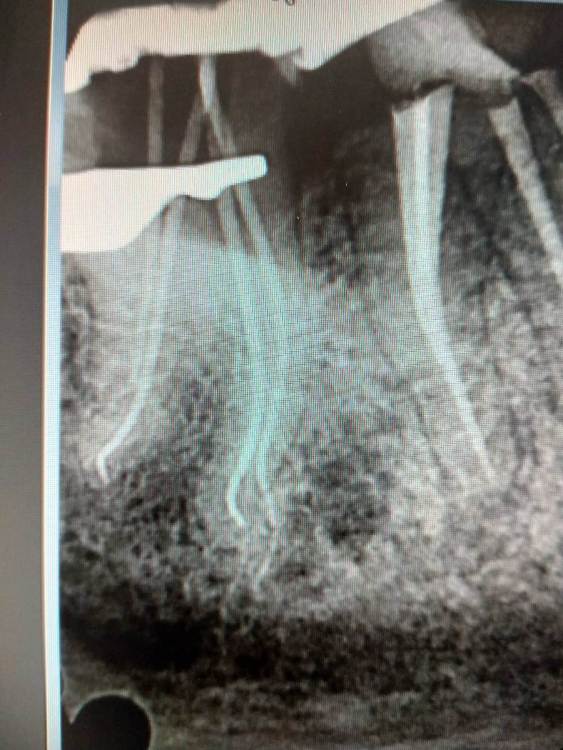

4.7 пульпит.2 визита SX -> S1 короткий -> scout -> Coco+2 плюс патфаилы 1-2 номер, иногда даже в ручном режиме до "0" по аплоку, финиш на 25.02 профайл руками.Гибридная паковка с  эйчем.

1.1.jpg